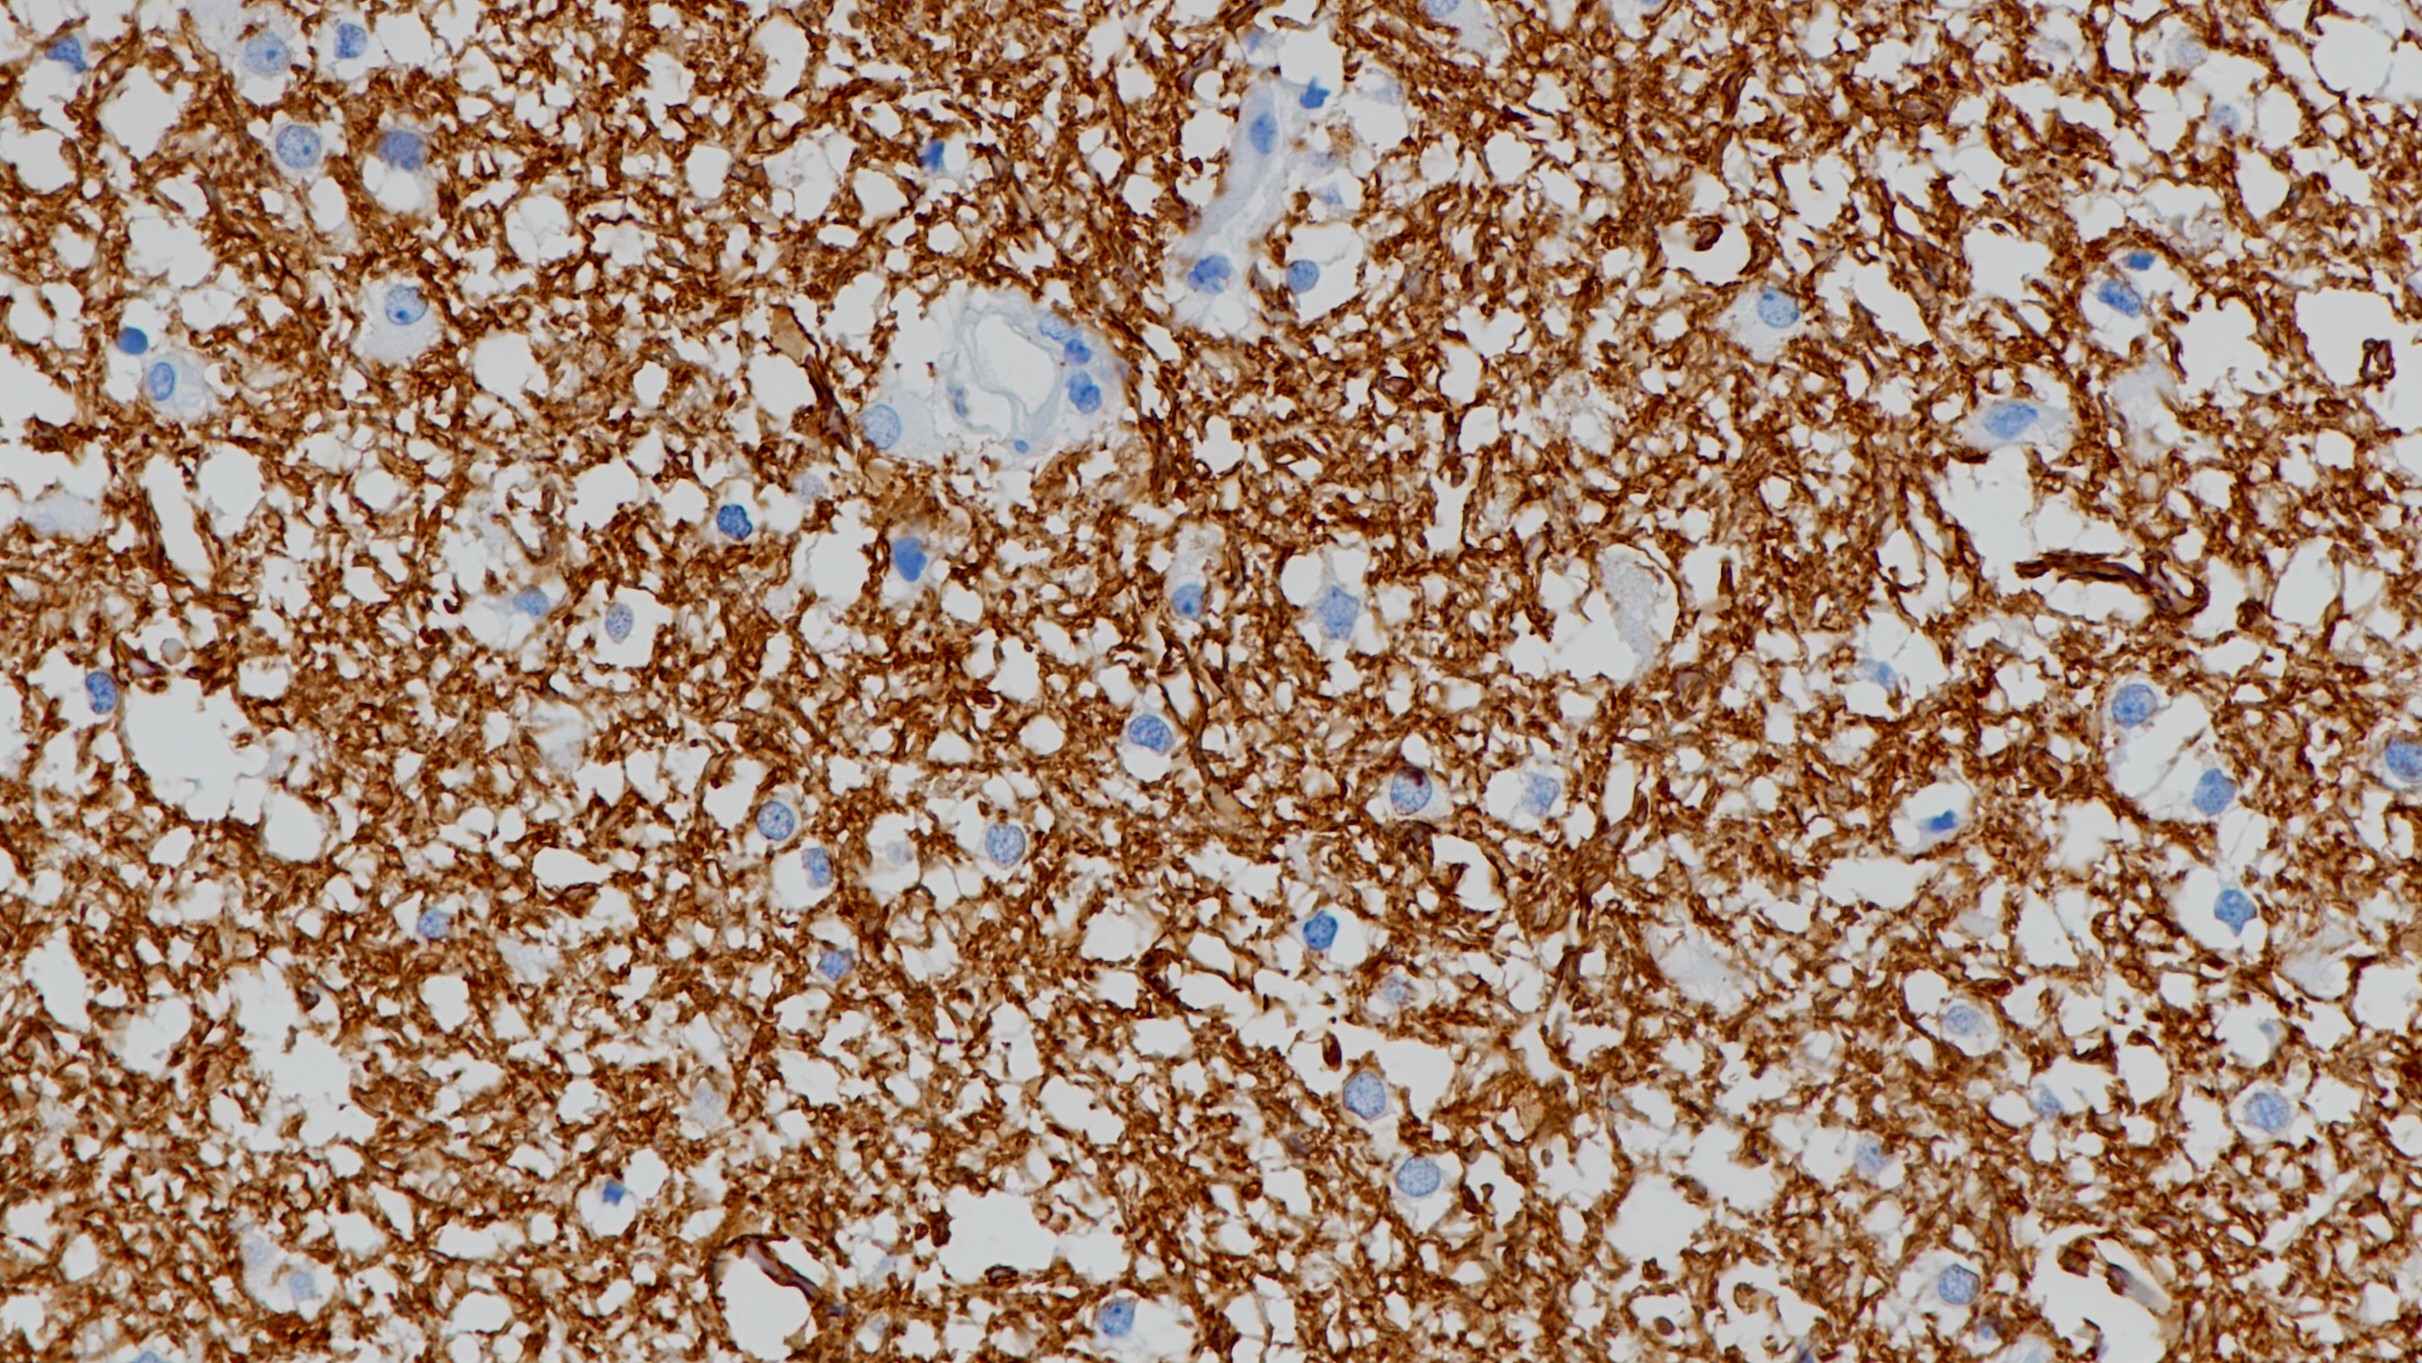

TdT是一种58kDa的DNA聚合酶,位于细胞核内,可催化3’末端脱氧核苷的聚合反应。该抗体标记正常胸 腺和骨髓的前体B和T淋巴细胞。在成熟淋巴瘤的肿瘤细胞及急性淋巴细胞白血病中TdT呈高表达,有助于淋巴细胞白血病和霍奇金淋巴瘤的鉴别。

胸腺瘤